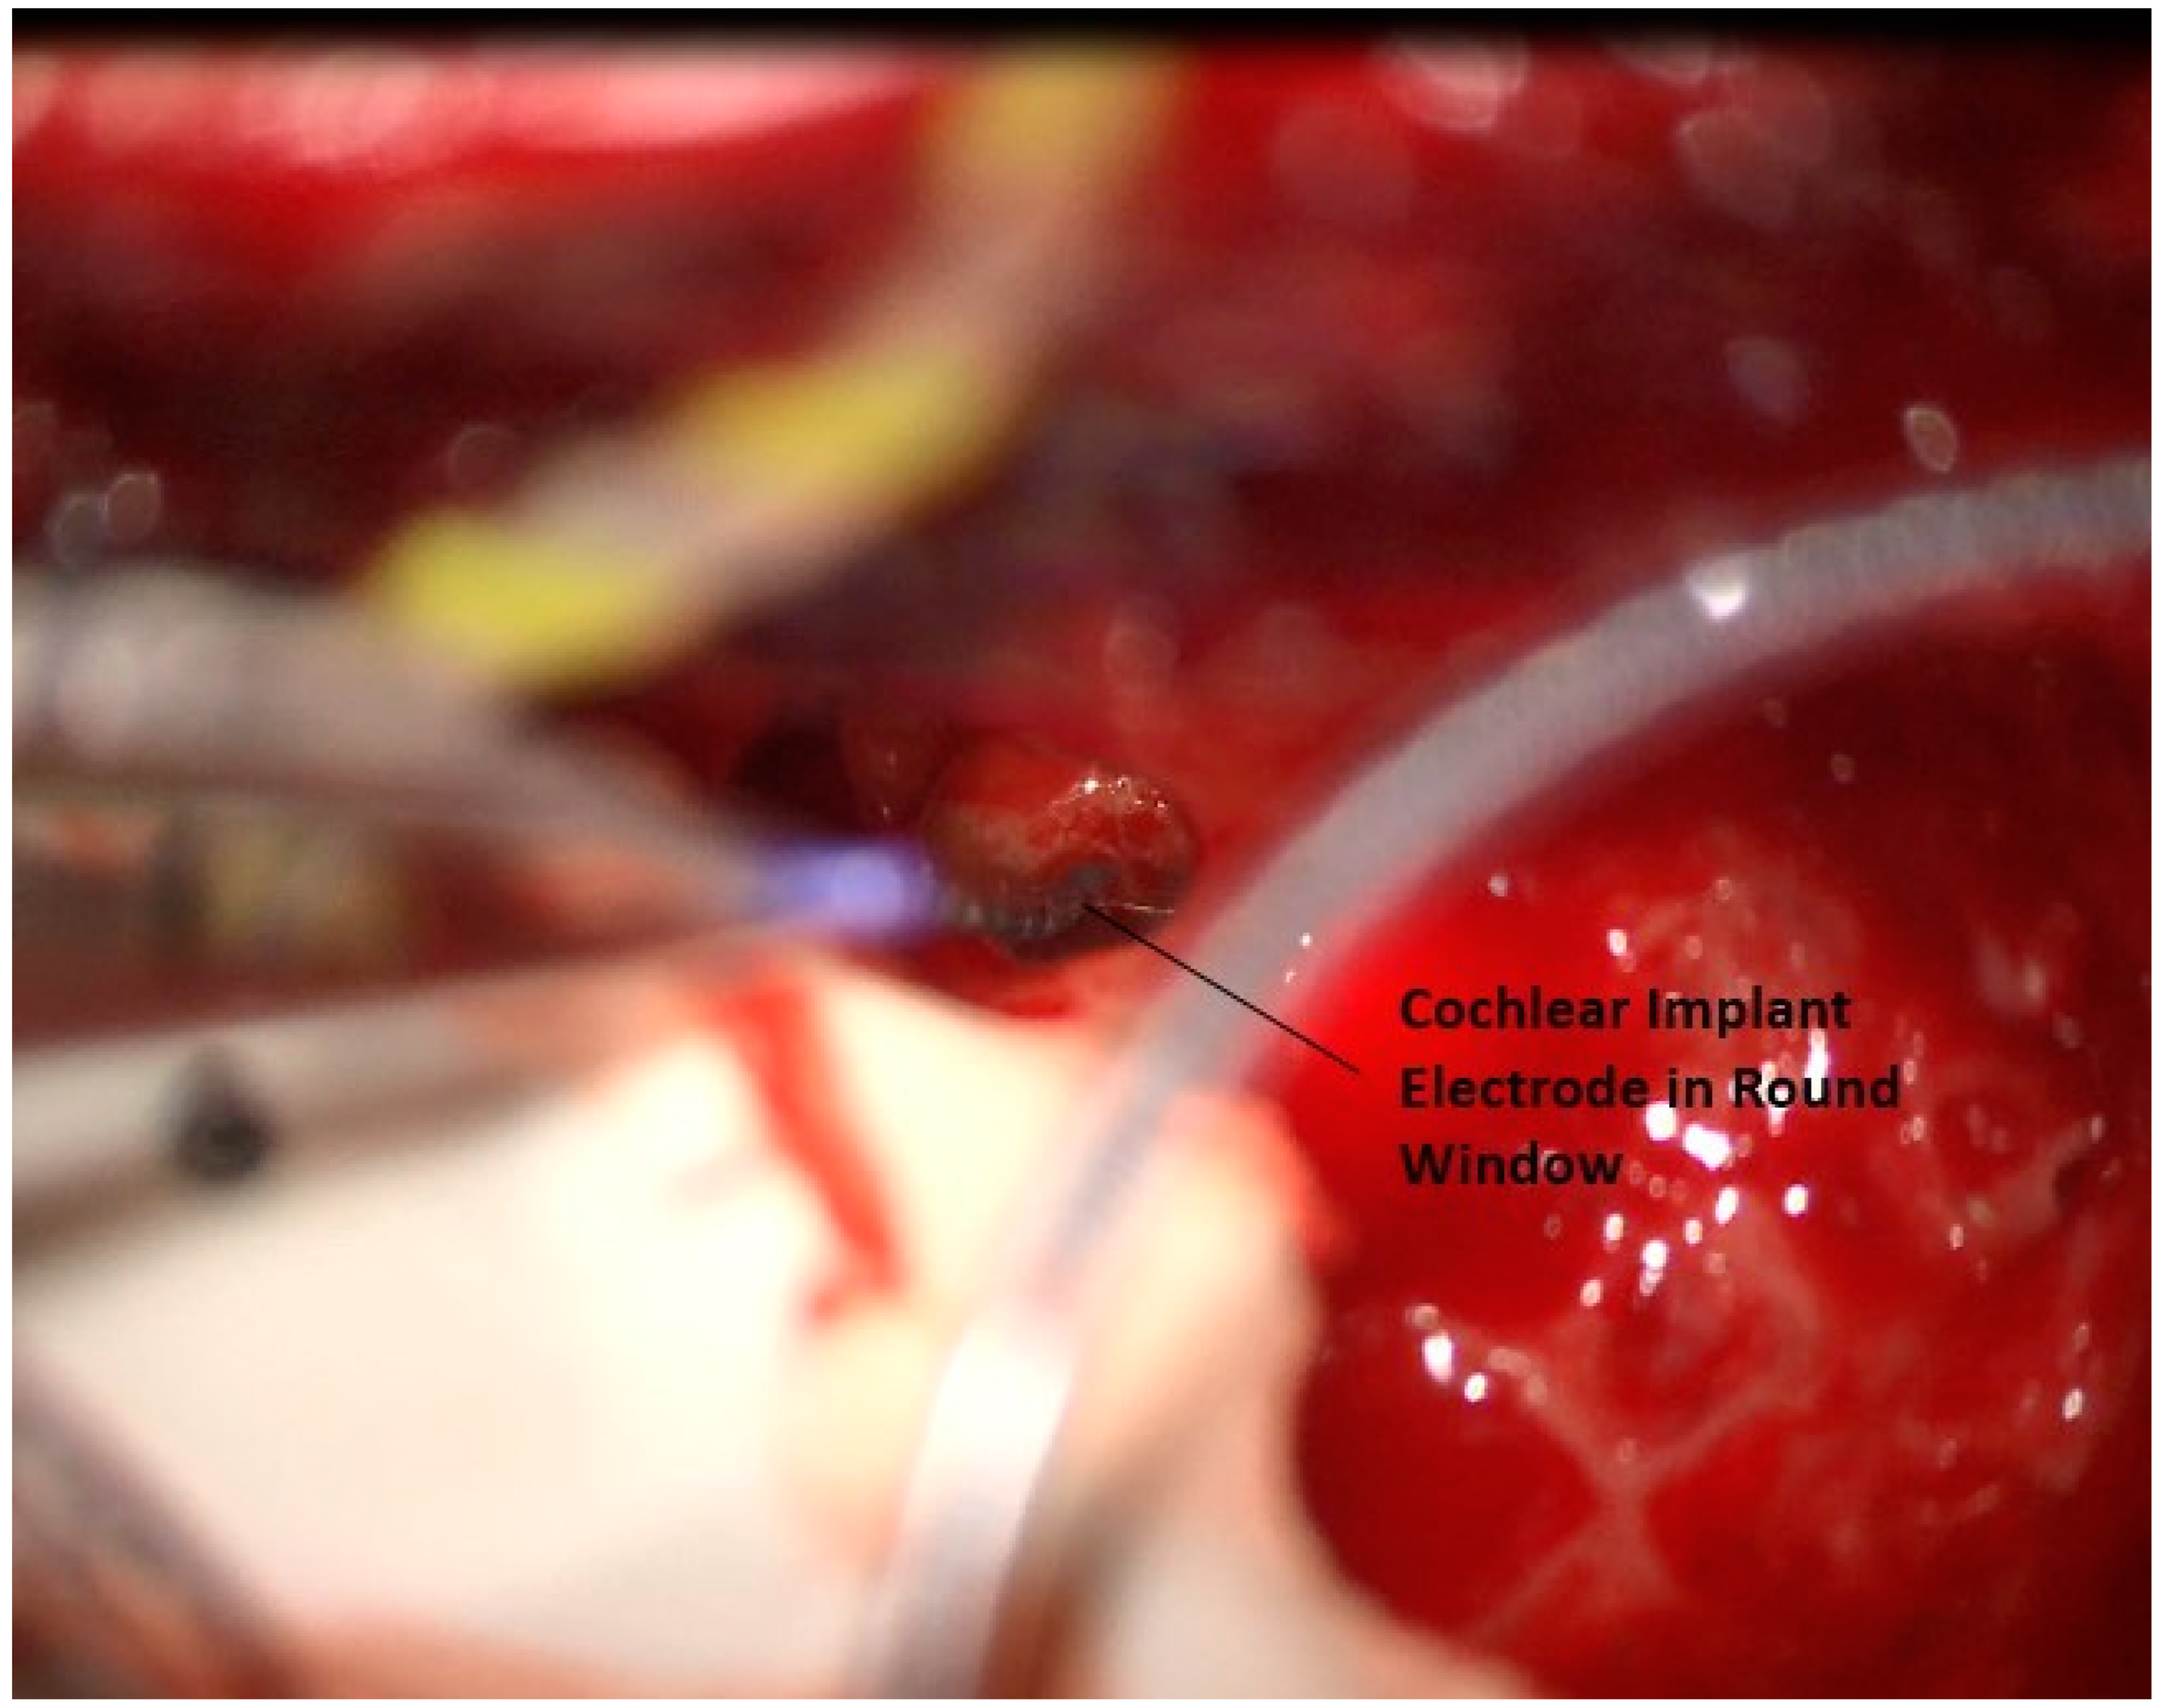

Any remaining round window niche that obstructs the surgeon’s view can be carefully drilled away, and the round window is opened. The electrode is then inserted (Figure 14). The current electrode design is a lateral wall array with 16 electrodes and is placed in the same fashion as similar devices from other companies. After a full-length insertion is completed, the round window is packed with muscle. At this point, both surgical sites are closed with absorbable stitches. Testing is then performed to confirm communication with the device, normal impedances, neural responses, and that a stapedial reflex is consistently elicited. An intraoperative X-ray is obtained to confirm the appropriate positioning of the electrode array. In all three patients, intraoperative testing was normal.

Figure 14. Placement of electrode through round window.